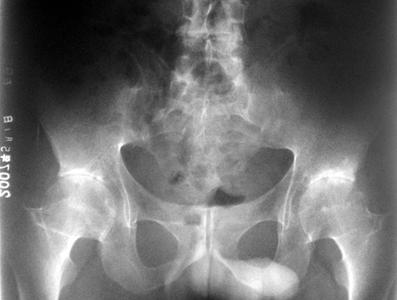

X线检查是确定患者 强直性脊柱炎症状 的重要检查项目之一,它对确诊强直性脊柱炎的重要意义,通过X线检查可见关节、脊柱的变化,而不同关节的X线检查也会有不同的改变。下面由贵阳风湿病中医院的专家为大家详细介绍强直性脊柱炎X线检查都有哪些可见症状: 强...[详细] 2025-01-03